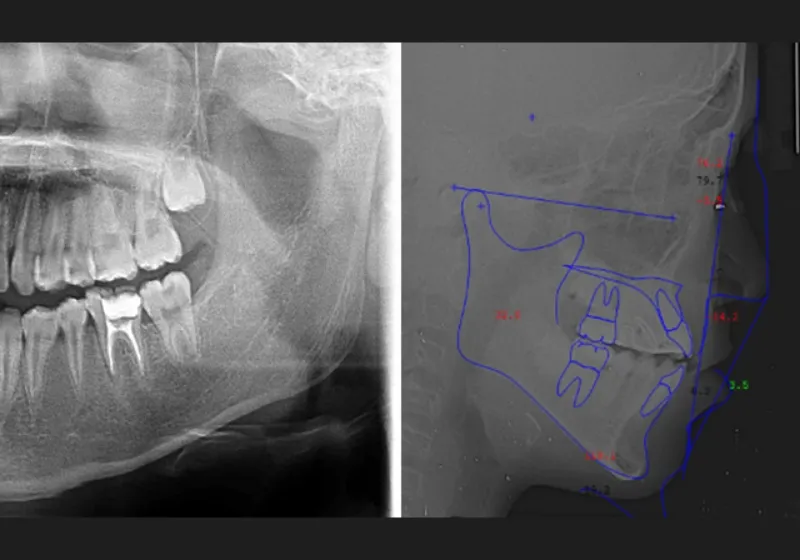

患者さまの診断に必要なデータをそろえるため、歯型採取、顔貌や口腔内の写真撮影、パノラマレントゲン写真撮影、頭部X線規格写真撮影、虫歯・歯周病の検査などを行ないます。